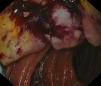

Varón de 49 años con extirpación de melanoma nodular estadio IIA en el brazo izquierdo hace 2 años. Acude por dolor abdominal epigástrico de 2 semanas de evolución, fiebre nocturna y síndrome constitucional. Analíticamente destaca anemia microcítica: hemoglobina 8.9g/dl, volumen corpuscular medio 73.7fl; elevación de proteína C reactiva: 220mg/l. La tomografía computarizada (TC) abdominal describe dilatación aneurismática intestinal junto a múltiples adenopatías regionales mesentéricas (figs. 1 y 2). Ante los hallazgos se realiza enteroscopia con doble balón donde se aprecia masa ulcerada, friable y dura a la toma de biopsias en primera porción yeyunal (fig. 3). En el diagnóstico diferencial también incluimos el linfoma primario intestinal, el tumor estromal gastrointestinal (GIST), el leiomiosarcoma y el adenocarcinoma. El estudio histopatológico concluye como metástasis intestinal de melanoma (figs. 4 y 5). Se realiza resección intestinal del segmento afecto y posterior inmunoterapia con nivolumab. La mayoría de los melanomas intestinales son metástasis de un melanoma cutáneo primario, con mejor pronóstico. En este caso, los antecedentes, los hallazgos endoscópicos y el análisis histopatológico aclararon el diagnóstico definitivo.